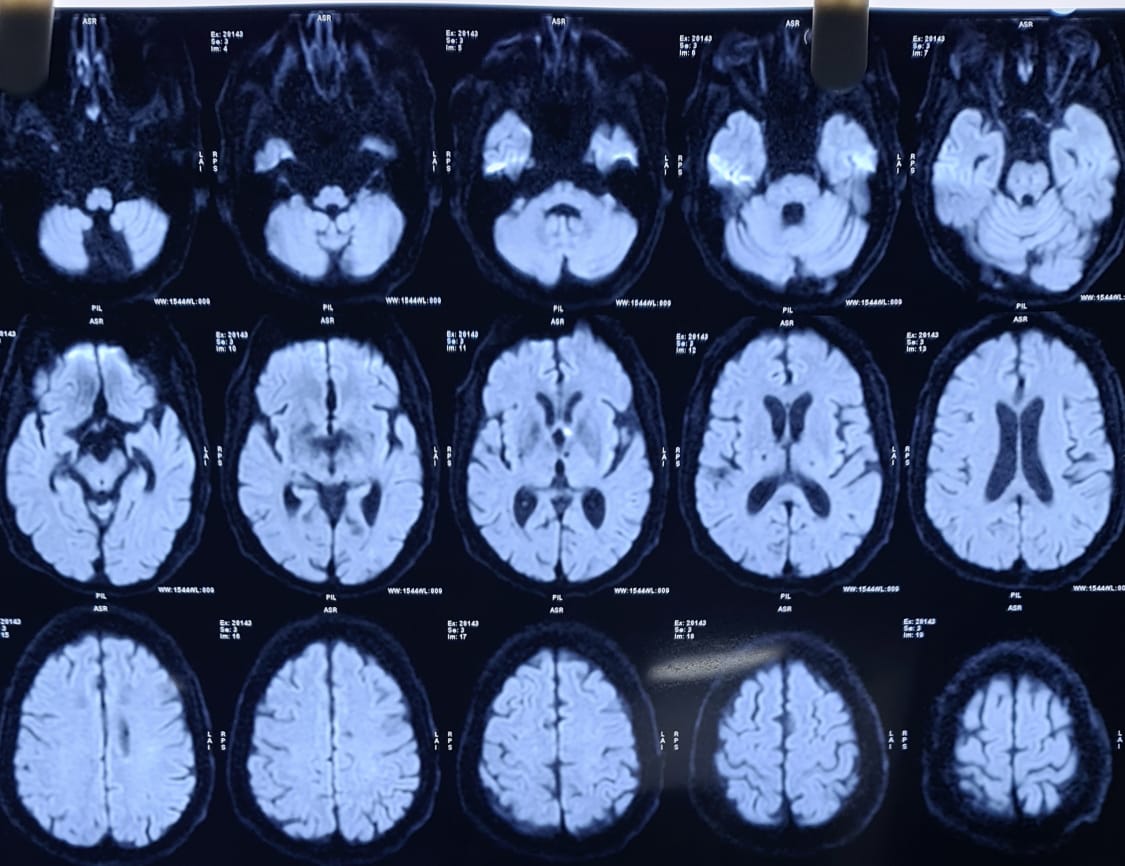

WEEK 2 : MIDBRAIN INFARCT

3RD NERVE PALSY